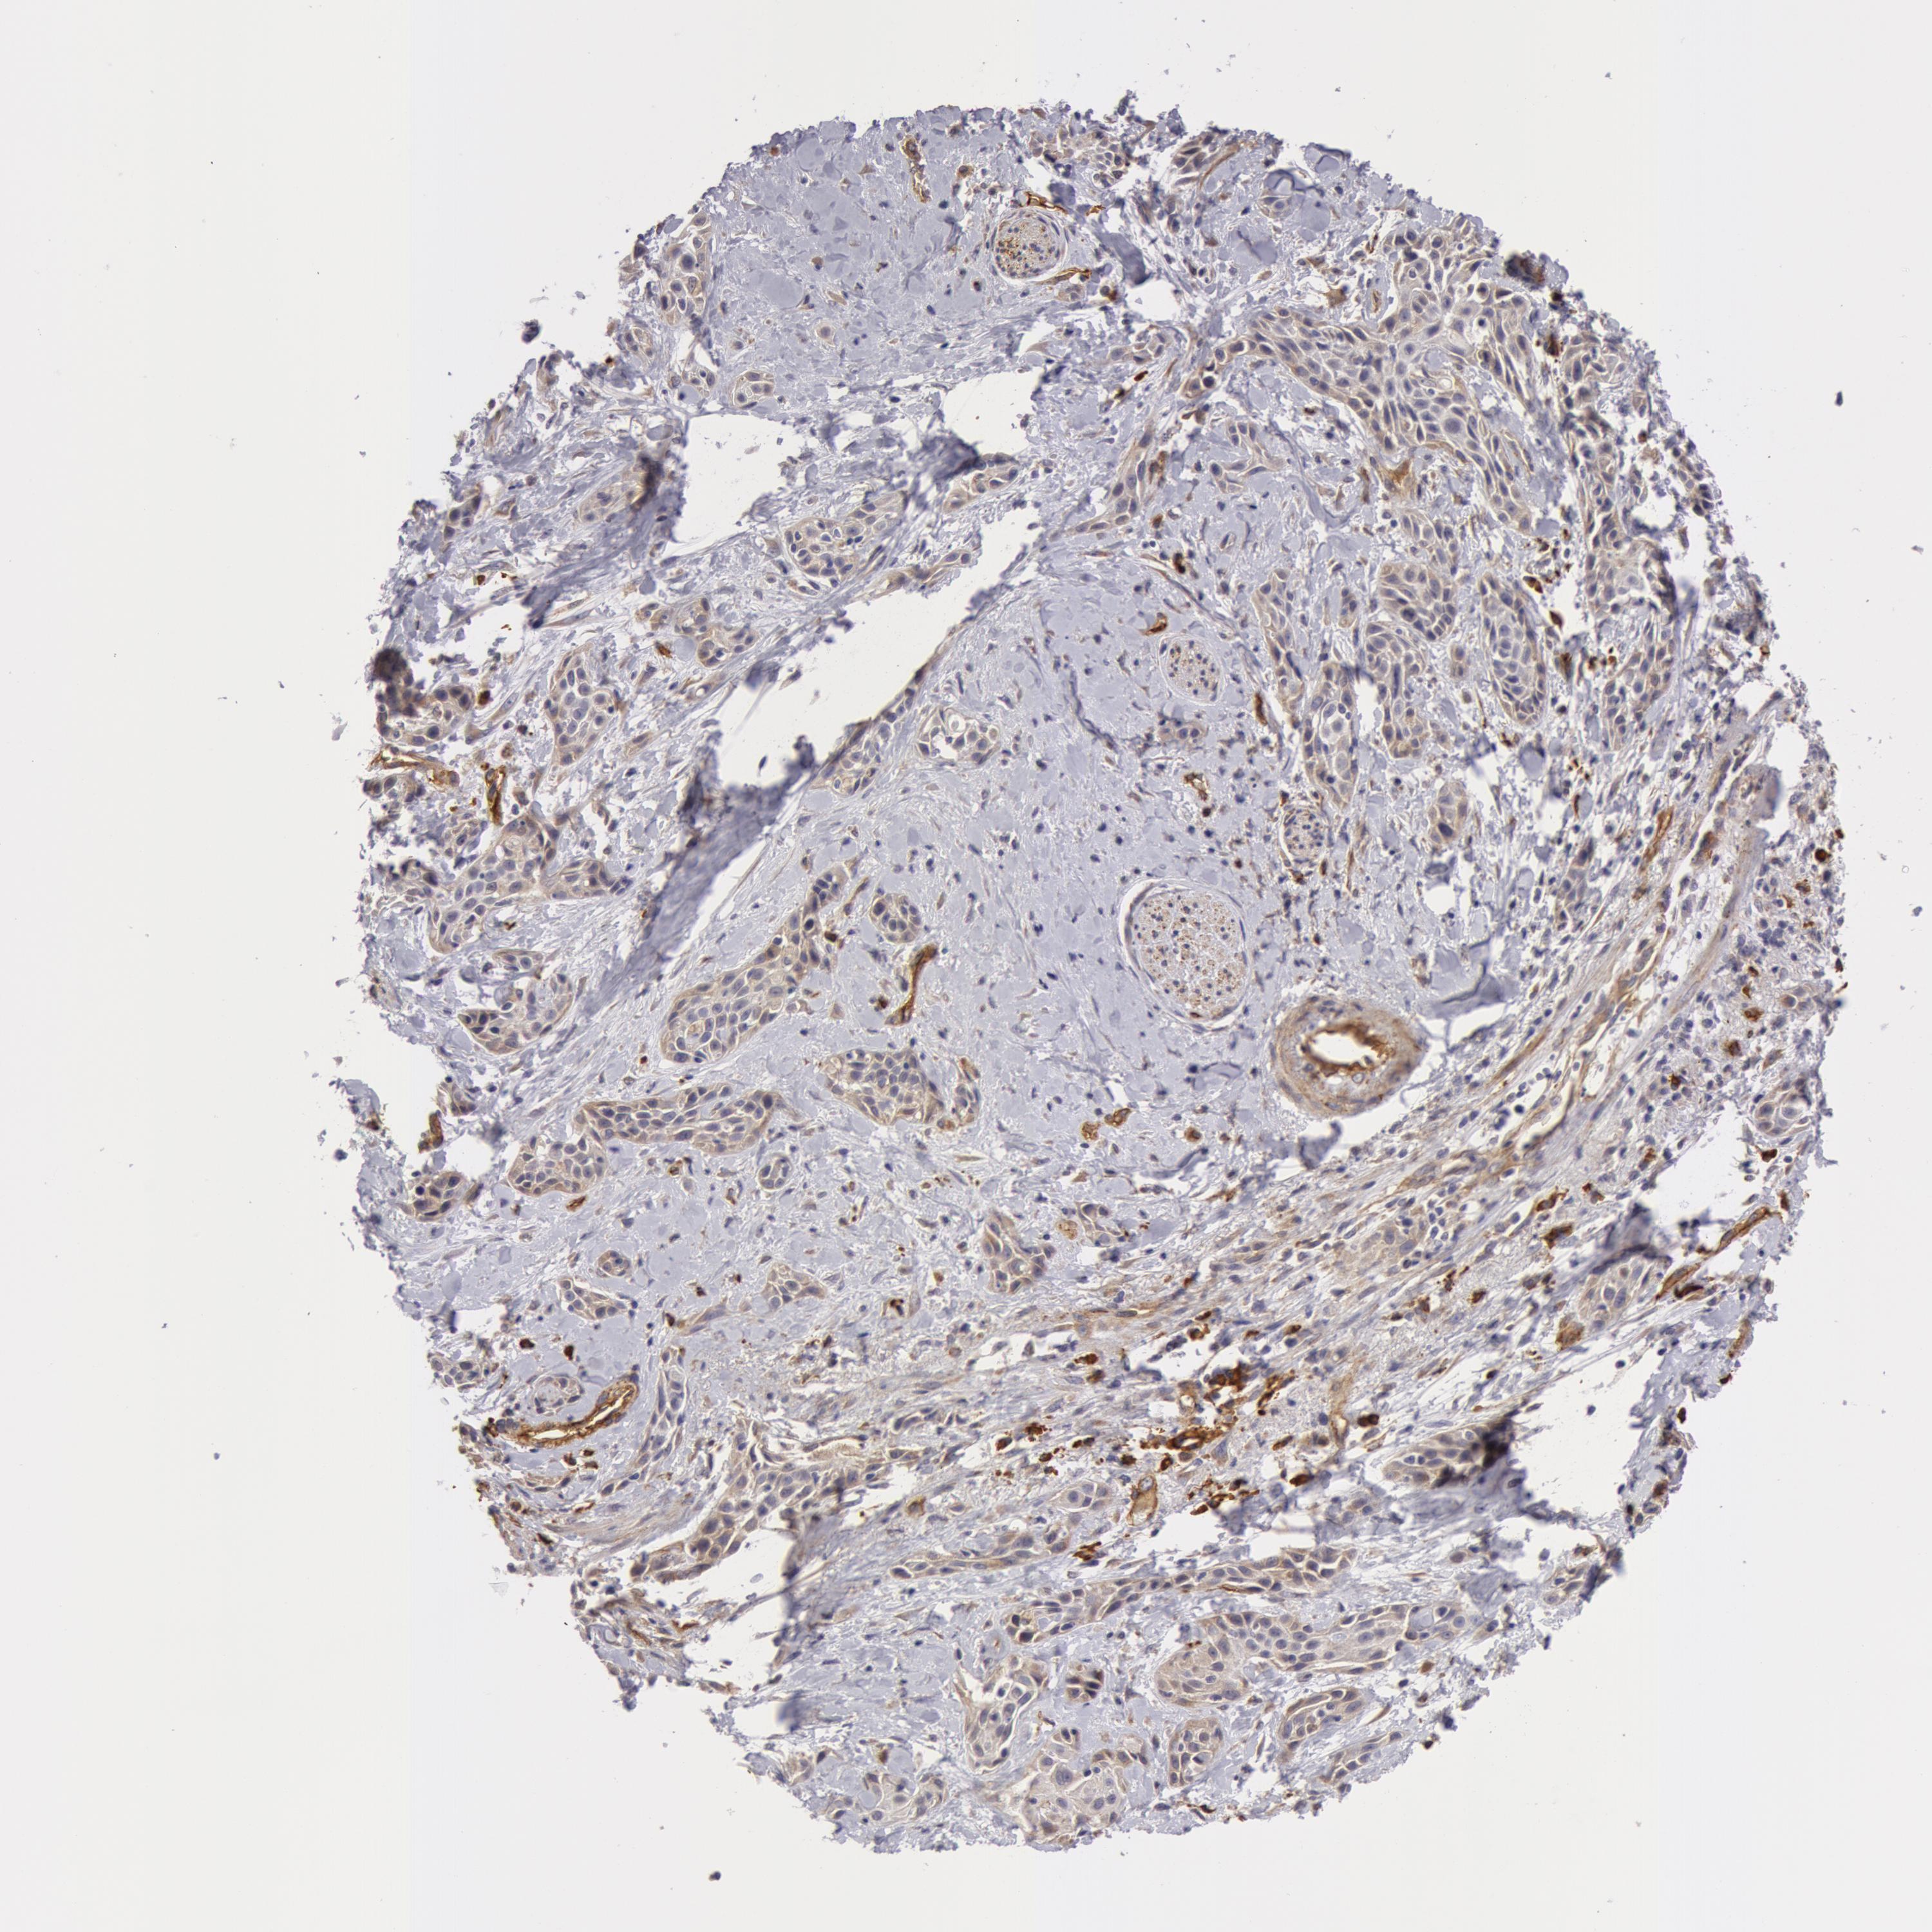

SKIN CANCER - Protein expressioni

A mouse-over function shows sample information and annotation data. Click on an image to view it in a full screen mode. Samples can be filtered based on level of antibody staining by selecting one or several of the following categories: high, medium, low and not detected. The assay and annotation is described here.

Antibody stainingi

Antibody staining in the annotated cell types in the current human tissue is reported as not detected, low, medium, or high, based on conventional immunohistochemistry profiling in selected tissues. This score is based on the combination of the staining intensity and fraction of stained cells.

Each image is clickable and will lead to virtual microscopy that enables deeper exploration of all samples and also displays staining intensity scores, fraction scores and subcellular localization as well as patient and tissue information for each sample.

Antibody HPA001554

Staining

High

Medium

Low

Not detected

Intensity

Strong

Moderate

Weak

Negative

Quantity

>75%

75%-25%

<25%

None

Location

Nuclear

Cytoplasmic/membranous

Cytoplasmic/membranous,nuclear

Squamous cell carcinoma, NOS

Basal cell carcinoma